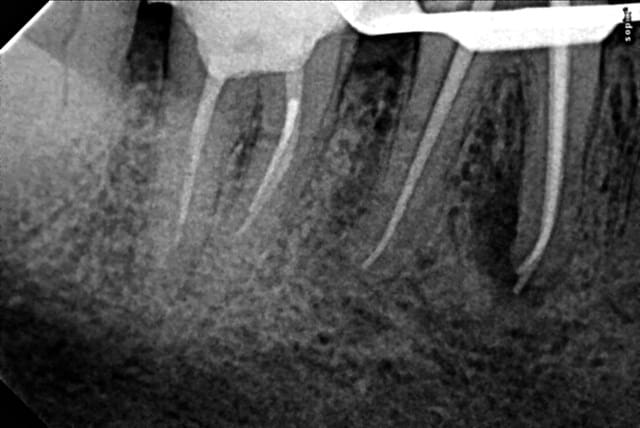

Il ne faut pas forcer pour extraire simplement insérer l'élévateur au bon endroit (enfin bon je l'ai bien dé calottée la couronne ( mouvement de l'avant bras proche de celui qu'on fait quand on essaye de faire une gamelle au baby foot) avant de séparer les racines mais des fois tout vient en meme temps lol !) . C'est au moment de soulever la racine distale que j'avais mobilisée qu'elle s'est fait la malle. -)

cette racine me parait très bien ou elle est.

Pourquoi la chercher? (rapport avantages inconvénients)

Je la laisserais bien à sa place (sauf si la pulpe était nécrosée bien sûr)et j'attendrais....

ça risque de faire un bel implant naturel et....c'est tout